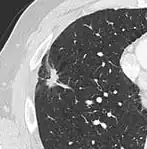

If there is an intermediate risk of malignancy, further imaging with positron emission tomography (PET scan) is appropriate (if available). It can be done simultaneously as a CT scan in the form of PET-CT. Around 95% of patients with a malignant nodule will have an abnormal PET scan, while around 78% of patients with a benign nodule will look normal on PET (this is the test sensitivity and specificity).[15] Thus, an abnormal PET scan will reliably pick up cancer, but several other types of nodules (inflammatory or infectious, for example) will also show up on a PET scan. If the nodule has a diameter of less than one centimeter, PET scans are often avoided because of an increased risk of falsely normal results.[15][16][17] Cancerous lesions usually have a high metabolism on PET, as demonstrated by their high uptake of FDG (a radioactive sugar).

-

PET-CT of a tuberculoma.